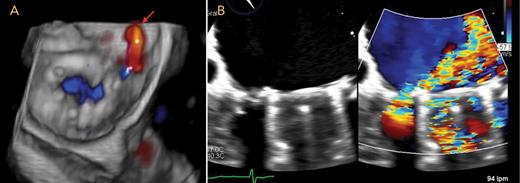

Point-of-care cardiac ultrasonography, performed in the emergency room, revealed normal biventricular function and no evidence of pericardial effusion or clot on the mitral valve. Transesophageal echocardiography showed signs of valvular prosthesis dysfunction, with a paravalvular leak on a posterior ring (Figure). This leak was likely due to the poor quality of tissues, which were friable due to the active infectious process when the valve was implanted. The patient was on transfusion support during the intervention. In the first few days after the procedure, hemolysis improved, with the patient’s LDH measuring 391 IU/L, total bilirubin at 1 mg/dL, and hemoglobin at 8 g/dL.

Images from three-dimensional transesophageal echocardiography

A: View of the mitral prosthesis from the left atrial aspect, with paravalvular regurgitation depicted with color Doppler, located posterolaterally (arrow). B: Mitral regurgitation with and without color Doppler.